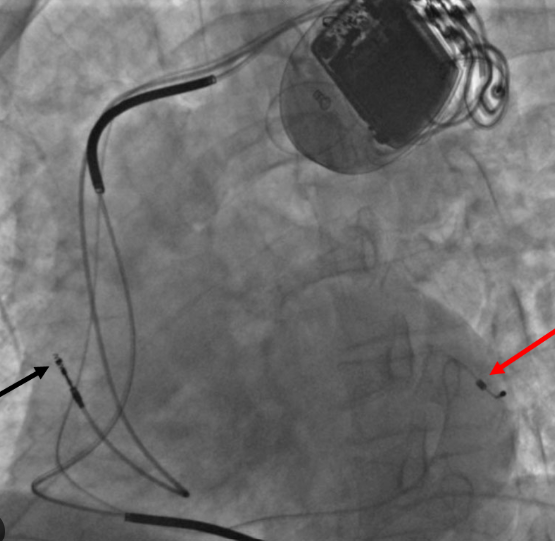

A CRTD (Cardiac Resynchronization Therapy with Defibrillator) is a small, battery-powered device implanted under the skin near the chest that helps the heart beat more efficiently. It performs two main functions:

- Cardiac Resynchronization Therapy (CRT):

The CRT component coordinates the contractions of the left and right ventricles using tiny electrical impulses, allowing the heart to pump blood more effectively. - Implantable Cardioverter Defibrillator (ICD):

The ICD function monitors the heart rhythm continuously and delivers a life-saving shock if it detects a dangerously fast or irregular rhythm, preventing sudden cardiac death.

- Accurate lead placement guided by high-resolution imaging